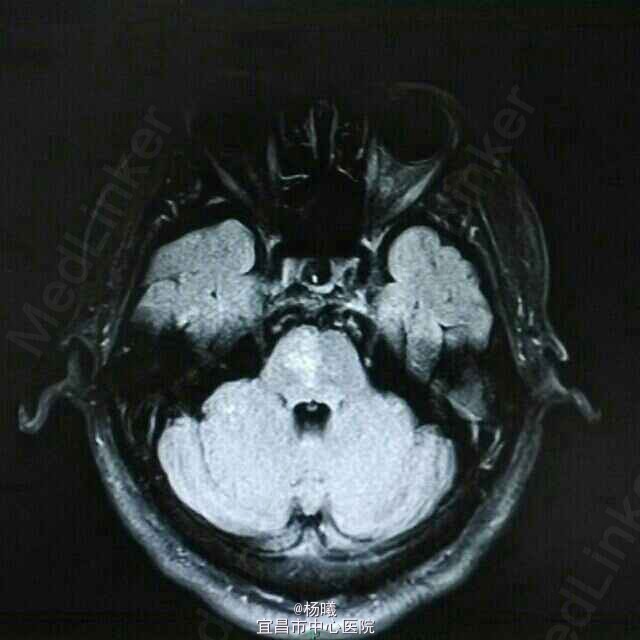

查体:BP 136/84mmHg,抬腿右下肢较左侧差,余无明显异常。 辅检:6-8 D-D 1.87,FIB 7.15,ALT 38,AST 46,GGT 37,LDL-C 4.38,铁蛋白 320,CRP 96.7,ESR 70,尿酮体1+ 6-15 PLT 469,ALT 53,GGT 50,ESR 38,D-D 0.59 血糖监测:早餐后高 彩超多普勒:升主动脉较宽,左室舒张功能减低;双侧颈动脉粥样硬化斑形成。 经颅多普勒:双侧颈内动脉、颈外动脉、左侧颈总动脉血流速度减慢;左侧锁骨下动脉、右侧大脑中动脉、大脑前动脉、左侧颈内动脉虹吸部管腔呈收缩状态;左侧颈内动脉虹吸部管腔重度狭窄;各检查动脉管腔应硬化。 头部MR、脑动脉造影MRA:脑干右侧11*12mm梗塞灶;腔隙性脑梗塞;脑萎缩;双侧额部顶部硬膜下积液;左侧椎动脉起始段及椎动脉-基底动脉汇合段管腔中度狭窄,双侧颈总、颈内外动脉、双侧大脑前中后动脉多发中-重度狭窄,动脉粥样硬化表现。

诊断:脑梗塞;高血压病3级 极高危;糖尿病 2型;动脉粥样硬化;高脂血症;慢性胃炎 治疗:依达拉奉、马来酸桂哌齐特、丹森川穹嗪注射,小牛血清去蛋白注射液;硝苯地平缓释片;阿司匹林肠溶片;阿托伐他丁钙片;阿卡波糖片。